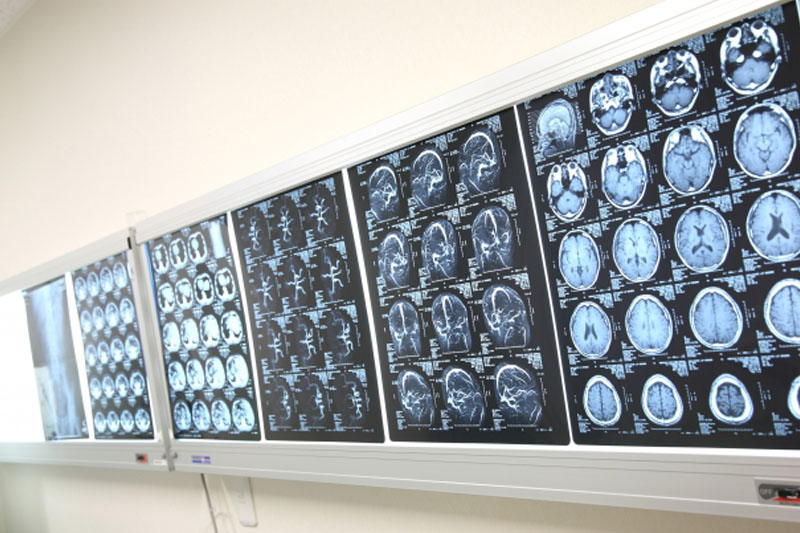

王杰後來轉到廣東三九腦科醫院求醫,該院的神經外二科副主任林濤立即安排王杰到深切治療部留醫,惟其病情惡化更陷入昏迷,並有四肢抽動、呼吸急促、瞳孔擴大等狀況。林濤指「初步診斷是細菌感染導致的硬膜下膿腫並形成腦疝」,「屬革蘭氏陰性桿菌感染」,故立即為王杰進行減壓手術和清除膿腫,最終手術順利成功。